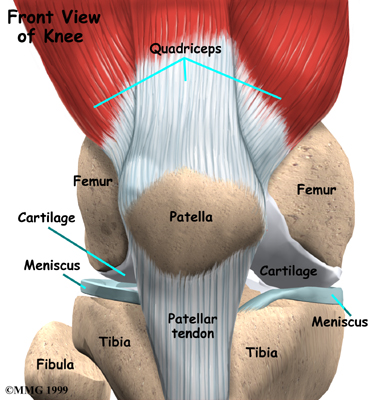

The knee joint is formed where the thighbone (femur) meets the shinbone (tibia). A slick cushion of articular cartilage covers the surface ends of both of these bones so that they slide against one another smoothly. The articular cartilage is kept slippery by joint fluid made by the joint lining (the synovial membrane). The fluid is contained in a soft tissue enclosure around the knee joint called the joint capsule.

Knee Joint